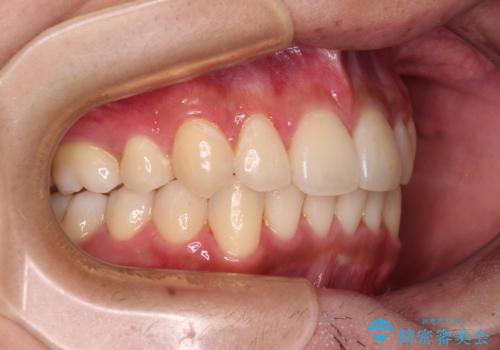

矯正治療の後戻りをインビザライン・ライトで解消

- 矯正治療の後戻りを気にして来院された患者様です。

後戻りは軽微であったので、インビザライン・ライトにより矯正治療を行うこととしました。

インビザライン・ライトは提供されるマウスピースの数に制限があり、通常のタイプよりもマウスピース提供期間が短くなっている一方、安価に治療を行うことができるプランです。

治療のゴールも変更できないため、軽微な歯列不正や、後戻り改善などに適しています。